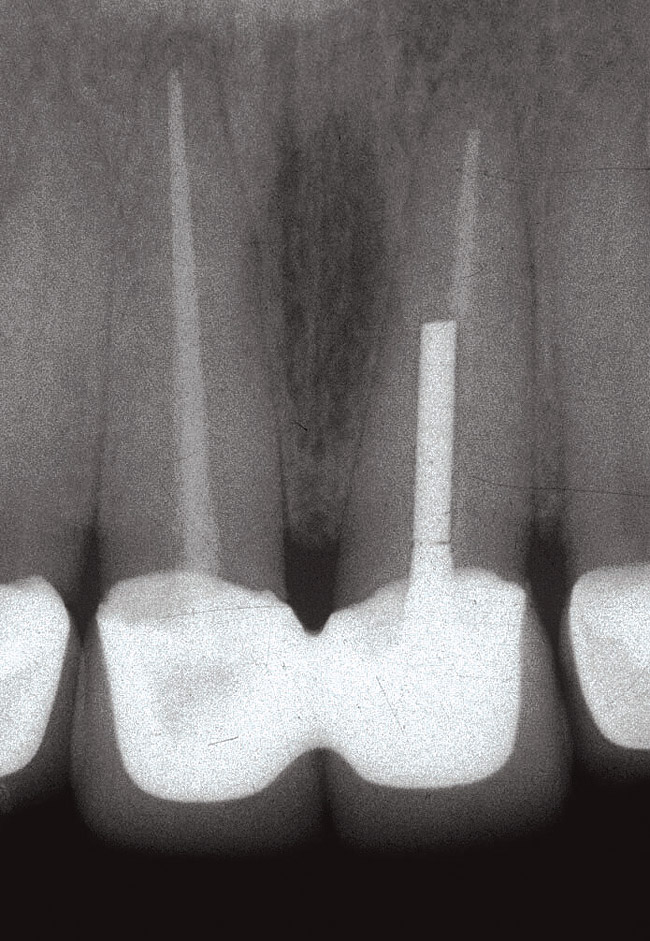

Fig 4. Initial radiograph.

Figure 4

Fig 5. Surgical placement of the implant with bone grafting as necessary.

Figure 5